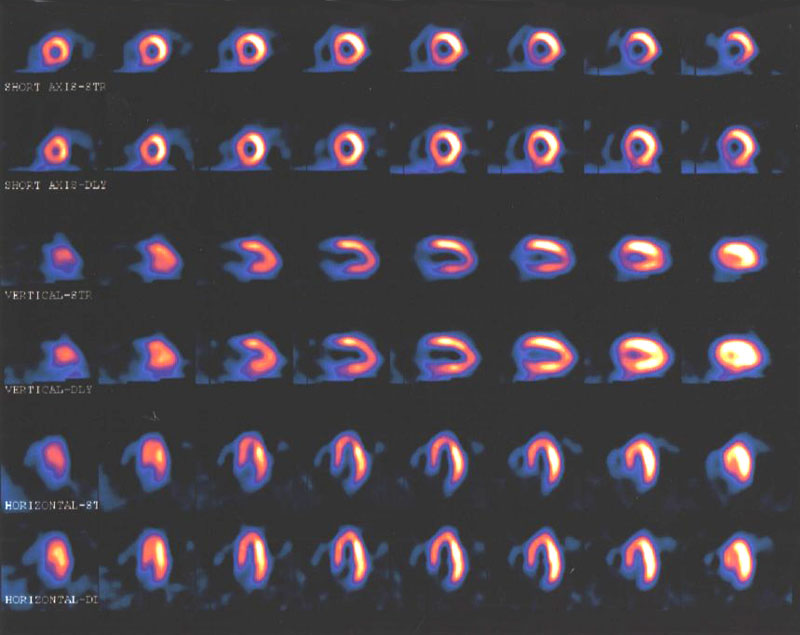

En pacientes con sospecha de enfermedad coronaria, la evaluación con resonancia magnética o gammagrafía de perfusión miocárdica permite reducir las angiografías innecesarias. JAMA, 29 de agosto de 2016